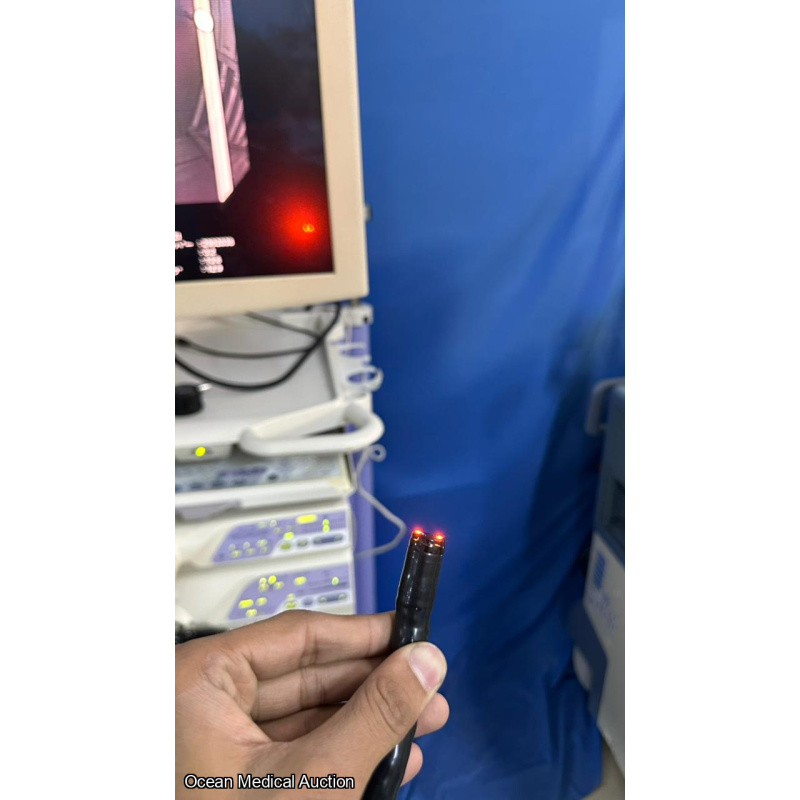

OLYMPUS CF-H260AZI SN.2902038 AND IT IS IN WORKING CONDITION